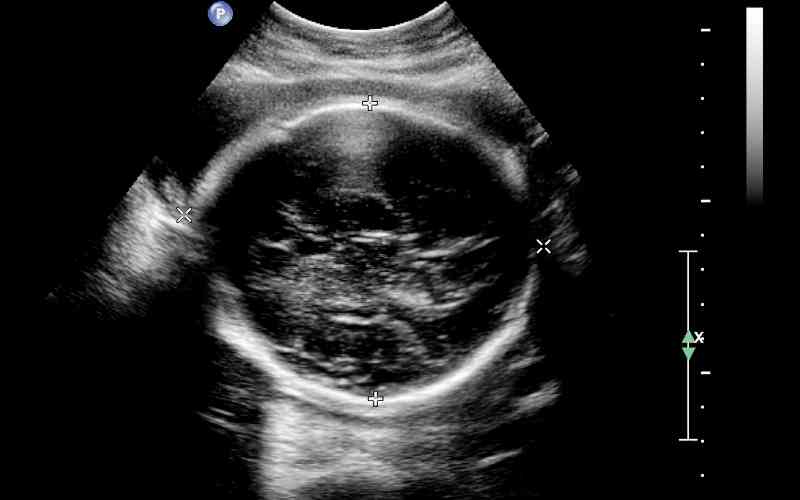

Siêu âm khi thai nhi được 6-8 tuần tuổi: Có thể nói đây là thời điểm siêu âm đầu tiên của mọi bà bầu để xác nhận chắc chắn mình có mang thai hay không. Nếu mang thai, bác sĩ siêu âm sẽ xác định tình tuổi thai, tình trạng phát triển và đã có tim thai hay chưa.

Siêu âm khi thai nhi được 11-13 tuần tuổi: Đây là thời điểm khám thai cực kỳ quan trọng không thể bỏ qua. Bởi các dị tật bẩm sinh về bất thường nhiễm sắc thể như: Hội chứng Down, Edwards và Patau sẽ được phát hiện chính xác thông qua phương pháp siêu âm đo độ mờ da gáy hoặc xét nghiệm Doubtest. Nếu phát hiện ra những bất thường gì, mẹ bầu cần giữ bình tĩnh và thực hiện theo hướng dẫn của bác sĩ.